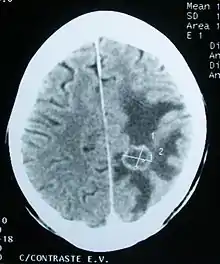

Imaging

Medical imaging plays a central role in the diagnosis of brain tumors. Early imaging methods – invasive and sometimes dangerous – such as pneumoencephalography and cerebral angiography have been abandoned in favor of non-invasive, high-resolution techniques, especially magnetic resonance imaging (MRI) and computed tomography (CT) scans,[39] though MRI is typically the reference standard used.[40] Neoplasms will often show as differently colored masses (also referred to as processes) in CT or MRI results.

- Benign brain tumors often show up as hypodense (darker than brain tissue) mass lesions on CT scans. On MRI, they appear either hypodense or isointense (same intensity as brain tissue) on T1-weighted scans, or hyperintense (brighter than brain tissue) on T2-weighted MRI, although the appearance is variable.

- Contrast agent uptake, sometimes in characteristic patterns, can be demonstrated on either CT or MRI scans in most malignant primary and metastatic brain tumors.

- Pressure areas where the brain tissue has been compressed by a tumor also appear hyperintense on T2-weighted scans and might indicate the presence a diffuse neoplasm due to an unclear outline. Swelling around the tumor known as peritumoral edema can also show a similar result.

This is because these tumors disrupt the normal functioning of the BBB and lead to an increase in its permeability. More recently, advancements have been made to increase the utility of MRI in providing physiological data that can help to inform diagnosis and prognosis. Perfusion Weighted Imaging (PWI) and Diffusion Weighted Imaging (DWI) are two MRI techniques that reviews have been shown to be useful in classifying tumors by grade, which was not previously viable using only structural imaging.[41] However, these techniques cannot alone diagnose high- versus low-grade gliomas, and thus the definitive diagnosis of brain tumor should only be confirmed by histological examination of tumor tissue samples obtained either by means of brain biopsy or open surgery. The histological examination is essential for determining the appropriate treatment and the correct prognosis. This examination, performed by a pathologist, typically has three stages: interoperative examination of fresh tissue, preliminary microscopic examination of prepared tissues, and follow-up examination of prepared tissues after immunohistochemical staining or genetic analysis.